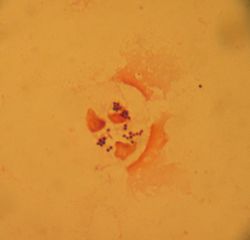

현미경으로 보면 포도송이처럼 여러 개체가 모여 있으며, 혈액 한천 배지에서 자랄 때 크고 둥근 황색 콜로니를 형성하고 때때로 용혈 현상을 보인다.[162] 분열법을 통해 무성으로 생식하며, 분열 마지막 단계에서 자가분해효소를 분비해 두 딸세포가 분리되는데, 이 효소가 충분히 분비되지 못하면 포도송이처럼 뭉쳐 자란다.[163]